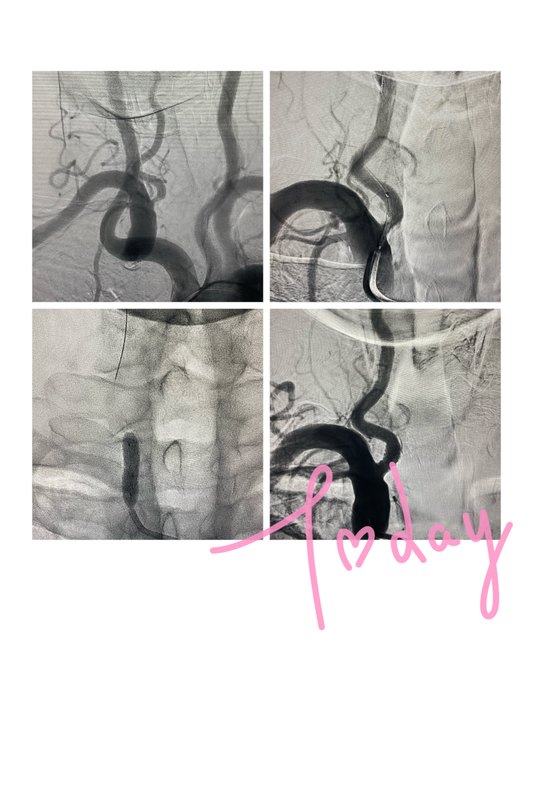

今日完成。58歲老年女性,有長期高血壓糖尿病病史,多發(fā)腦血管狹窄,頭暈1年余,加重1月。先后多處就診。造影,右側(cè)頸內(nèi)狹窄90%,左側(cè)頸內(nèi)狹窄60-70%,右椎動脈開口狹窄40%,右椎顱內(nèi)段整段纖細(xì),左椎動脈顱內(nèi)段纖細(xì),右側(cè)后交通動脈開放。后循環(huán)高危,通過后交通代償,迂曲明顯,暫不處理,通過開通右側(cè)頸內(nèi)動脈增加代償。左側(cè)頸內(nèi)動脈定期復(fù)查,若加重可考慮擇期再次手術(shù),避免同時開通高灌注。術(shù)中右頸內(nèi)保護(hù)傘通過后病人反應(yīng)遲鈍有缺血表現(xiàn),快速球囊擴(kuò)張支架植入后恢復(fù)正常。術(shù)后患者良好,控制血壓。